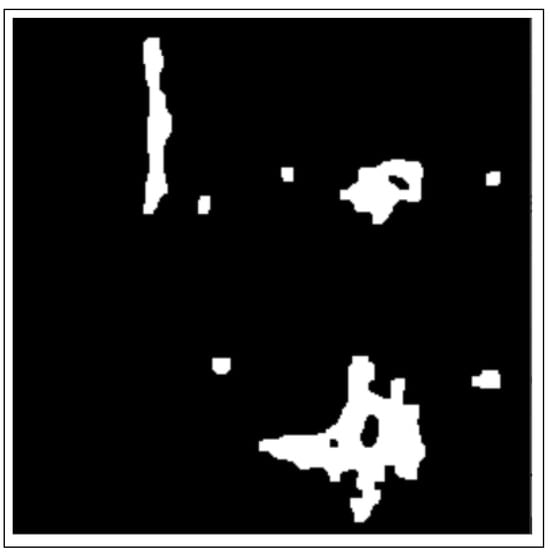

- Morphology operations enhance the image by highlighting important features. The connected components analysis method is used to group components with similar characteristics and assist in separating overlapping and non-overlapping objects.

3.2.1. Thresholding

3.2.2. Morphology Operations